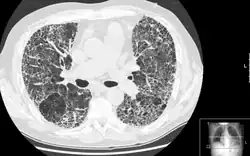

Po dokončení opravy tkáň se uvolnění od mechanického stresu a měla by přestat produkce myofibroblastů a již nepotřebné buňky skončí programovanou buněčnou smrtí. Mezi dva hlavní signály, které vedou k apoptóze myofibroblastů patří vytvoření mezibuněčných kontaktů a uvolnění stresových vláken. Pokud však tento signální mechanismus selže, tvorba myofibroblastů neustane a buňky nejsou odstraňovány, což vede k vzniku patologických jizev. Tyto jizvy poškozují vnitřní orgány, velmi často srdce, ledviny nebo plíce a vedou k fibrotickým onemocněním (např. plicní fibróza) nebo i vnější povrch těla, příkladem může být Dupuytrenova nemoc . [3] Pokud jizvy zůstanou na srdci, tvoří bariéru pro přenos elektrických signálů a mohou tedy vést k rozhození srdečního rytmu.